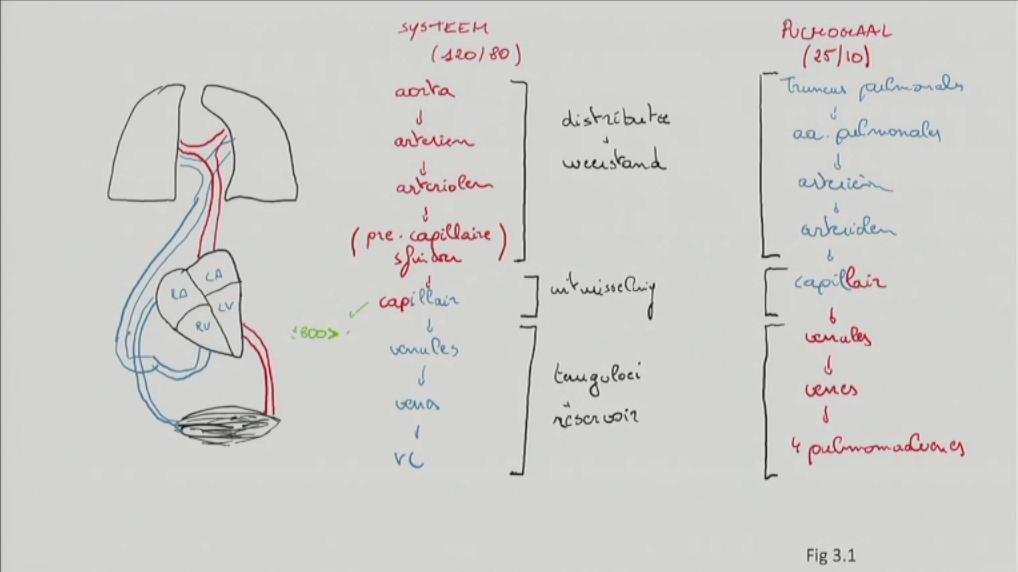

Fig 3.01: Schema grote en kleine bloedsomloop

atrium dextrum (RA) atrium sinistrum (LA) ventriculus dexter (RV) ventriculus sinister (LV)

arteries: weg van hart, onder hoge Druk venen: naar hart rood: zuurstofrijk bloed blauw: zuurstofarm bloed -

systeemcirculatie (120/80 mmHg)

distributie + weerstand

uitwisseling

terugvloei + reservoir

venules venen vv. cavae (x2)

pulmonaalcirculatie (25/10 mmHg, zelfde opdeling)

tr. pulmonalis aa. pulmonales arterien arteriolen capillair venules venen vv. pulmonales (x4)